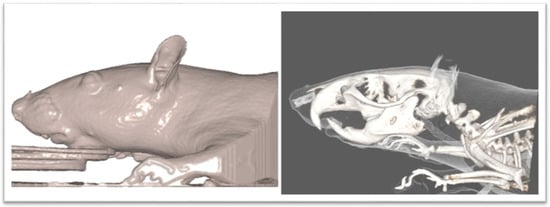

2. Materials and Methods